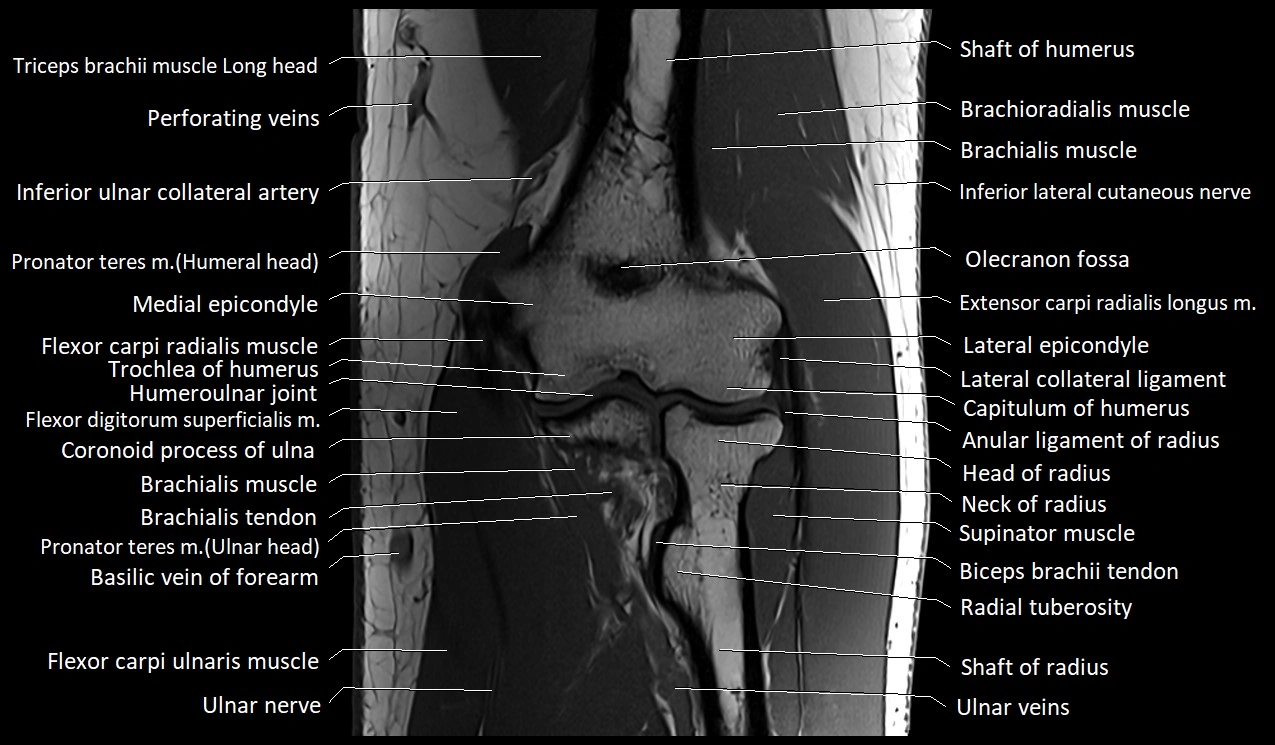

MRI image

image